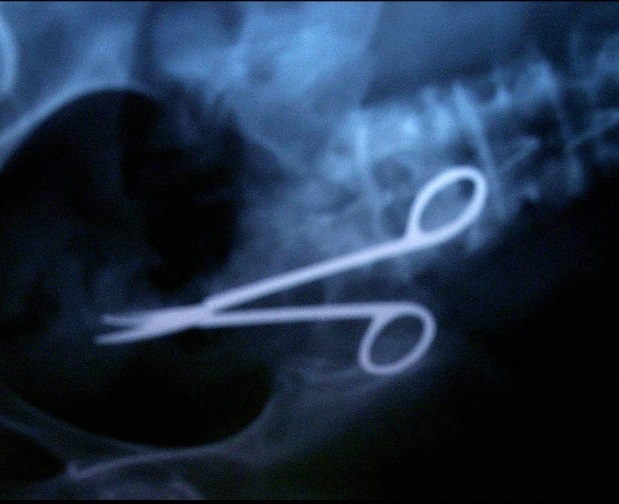

5. Quên dụng cụ y tế trong người bệnh nhân: Y tá có nhiệm vụ theo dõi, kiểm soát bao nhiêu dụng cụ dùng để phẫu thuật và phải chắc chắn có đúng bấy nhiêu dụng cụ sau khi thực hiện xong. Để quên dụng cụ phẫu thuật trong người bệnh nhân xảy ra ở 2/10.000 ca phẫu thuật. Nếu bạn bị đau đột ngột, sốt hoặc sưng sau khi phẫu thuật, hãy yêu cầu bác sĩ kiểm tra kỹ càng để chắc chắn không có dụng cụ nào trong người. |